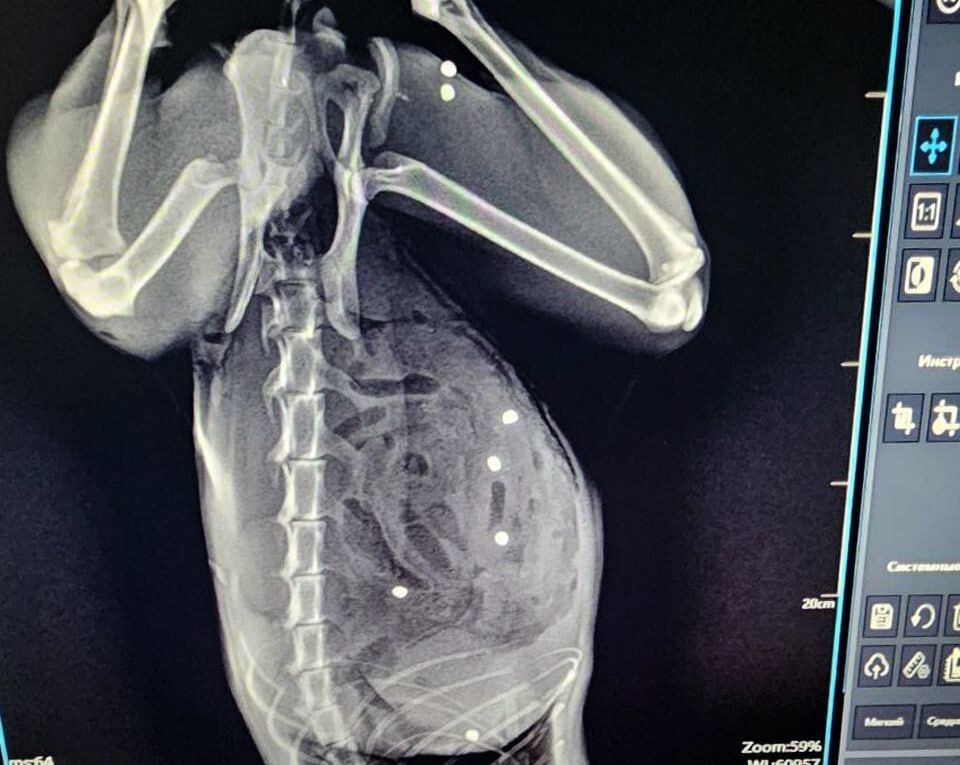

В Зеленограде ветеринары спасли пятилетнего кота Тимофея, получившего во время прогулки в частном секторе более 20 пулевых ранений.

У животного в 24 местах был пробит кишечник и в двух местах - селезенка. Также пули попали в грудную клетку и мышцы бедра. Операция длилась более трех часов. Пациента, которого считали почти безнадежным, спасли, сказано в сообщении."Под конец операции и кот, и я выглядели одинаково... Не скрою, горжусь собой на 100%, но ещё больше котом! Несмотря нa все усилия живодёров, котик жив!" - рассказал хирург